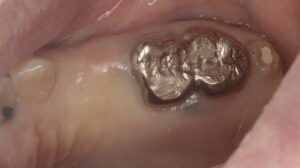

抜歯後しばらくしてからの写真とCT像です。今回は骨がまだできていない4番目の歯に左上奥に写っている親知らずを移植しもともと欠損だった5番目にインプラントを埋入する計画を立てました。